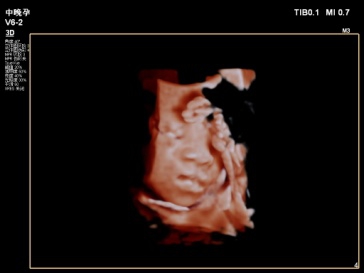

2019年我科室特引进飞利浦EPIQ5全身高档彩色多普勒超声,配备有心脏、腹部、浅表、腔内及三维容积等5把探头。其专有的purewave纯净波单晶技术,可提高在难以成像的患者身体中的穿透力,使成像更快捷、更清晰;飞利浦EPIQ5在孕期检查中也独具优势,通过图像的切割、旋转及高平面图像的分析,能直观、立体显示胎儿在母体子宫内的立体形态、表面特征、空间位置关系,尤其胎儿面部的三维成像,清晰、直观,准爸爸、准妈妈可以通过屏幕亲眼目睹胎儿的眼睛、嘴巴、鼻子和脸颊,甚至可以看到宝宝在妈妈肚子里运动、呼吸、吞咽、打哈欠、伸舌头等生理活动,非常直观。

每个孕妈妈都希望生个健康的宝宝,因此一定不要忘记这项重要的超声检查哦,不然错过时间可没有办法弥补了。我科室现已正式开展三维彩超,看这些可爱的宝宝!